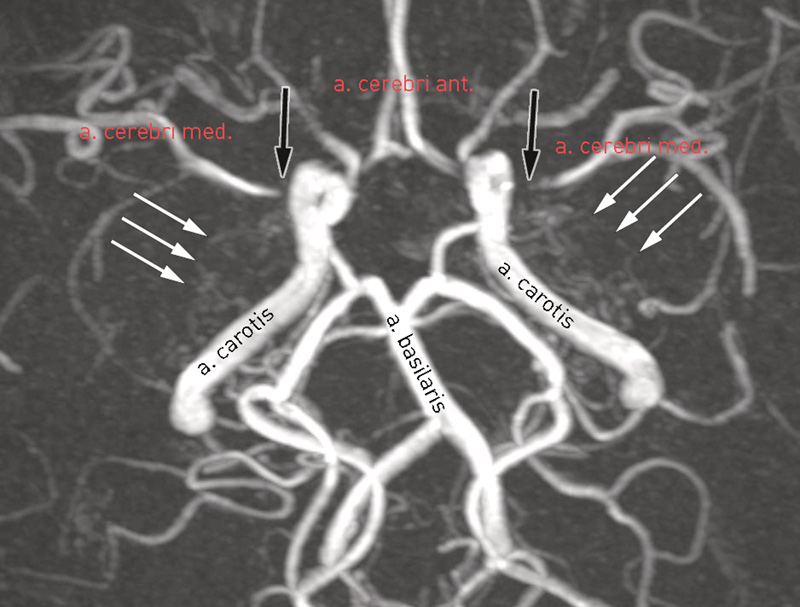

Et barn i skolealder ble innlagt etter en episode med forbigående afasi og hemiparese. Det ble gjort MR av hodet med angiografisekvenser som viste innsnevring av øvre deler av begge arteria carotis interna. På MR-bildet så man at stenosen fortsatte videre og omfattet proksimale deler av a. cerebri media (svarte piler). Rundt de trange partiene så man mange, små kollaterale blodkar (hvite piler).

Moyamoya er en sjelden sykdom i hjernens blodkar og innebærer en progressiv stenosering av toppen av a. carotis interna og de avgående arteriene fra Willis’ arterielle sirkel (1). Det oppstår en kompensatorisk utvikling av kollaterale kar. For å stille diagnosen vil man videre utføre en cerebral røntgenangiografi. Man vil da enda tydeligere se at dette karnettverket har et karakteristisk utseende som ofte sammenliknes med en «sky av røyk», som oversatt til japansk er «moyamoya». Tidligere har man trodd at sykdommen kun rammet personer av asiatisk opphav, men den er også blitt påvist på andre kontinenter. Årsaken er ukjent, men genetiske faktorer spiller trolig en viktig rolle. De vanligste symptomene som fører til diagnosen er episoder med nevrologiske utfall grunnet iskemi (transitoriske iskemiske anfall eller hjerneinfarkt), kramper, hodepine eller hjerneblødning. Ubehandlet har sykdommen en alvorlig prognose med høy risiko for gjentatte cerebrovaskulære hendelser (1).